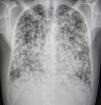

A chest X-ray was requested, showing multiple bilateral pulmonary nodules, most of which were cavitated (Fig. 1). Given the patient's history and the radiological findings, the initial diagnostic suspicion was tuberculosis, and additional tests and treatment were oriented towards an infectious process, but the patient did not improve.

The examination was completed with a computed tomography, which revealed innumerable pulmonary nodules, measuring between 1mm and 3.2cm, the vast majority of which were cavitated.

Multiple peribronchial lymphadenopathies were observed in both sides, along with a subcarinal lymph node mass, measuring 3.9cm, and a lymph node cluster in the right axilla.